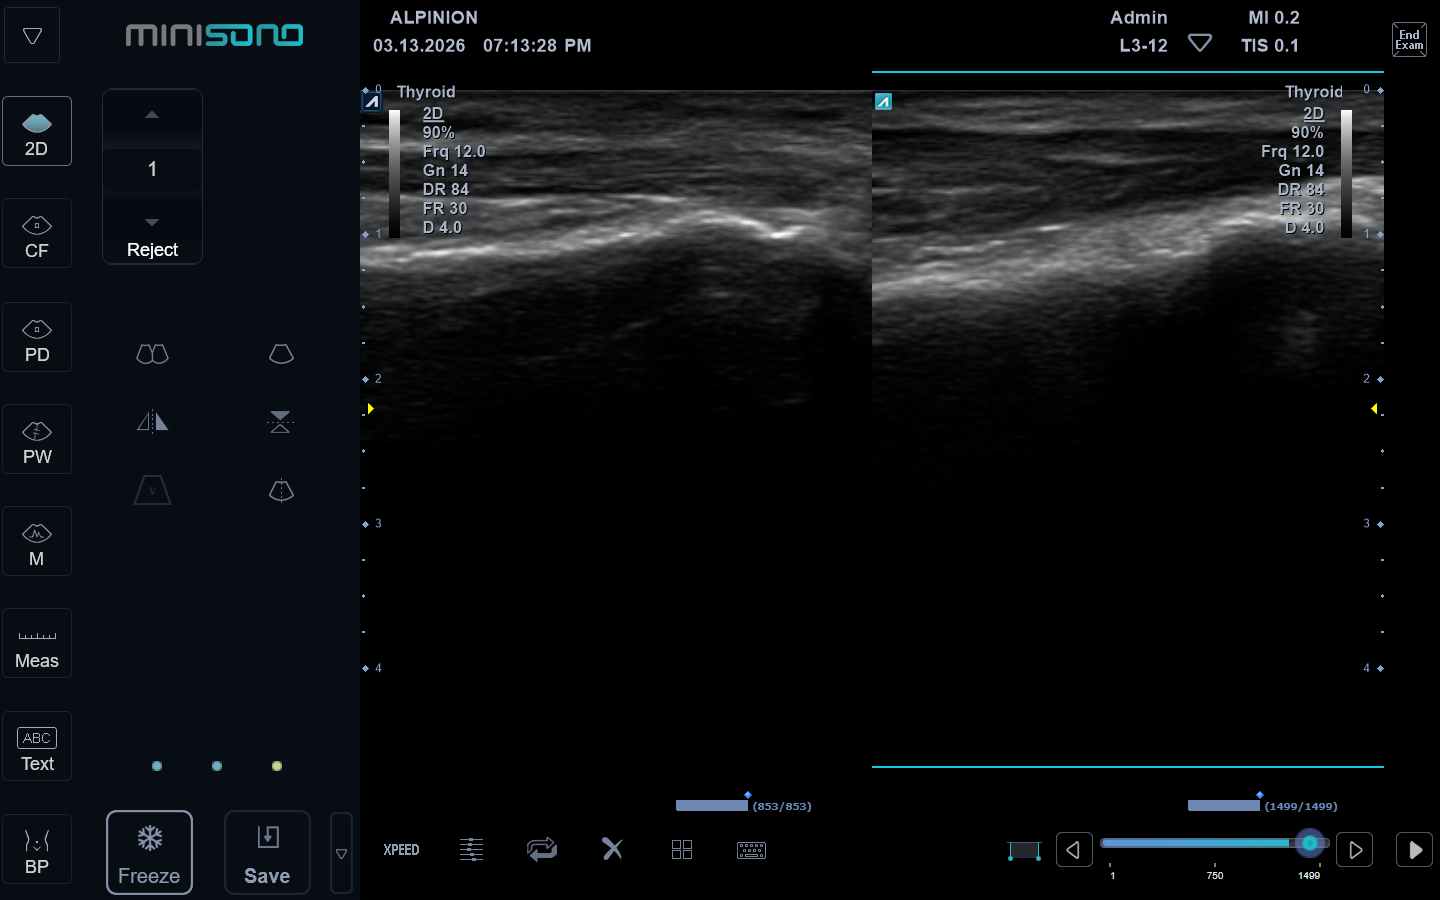

Bij klachten aan de voet of enkel is het soms belangrijk om goed te kunnen zien wat er in het lichaam gebeurt. Met echografie kunnen we spieren, pezen, banden en slijmbeurzen snel en pijnloos in beeld brengen.

Binnen Talstra Beweegt gebruik ik echografie als aanvulling op het fysiotherapeutisch en/of podologisch onderzoek. Zo krijgen we samen een duidelijker beeld van de oorzaak van de klacht en kunnen we de behandeling gerichter inzetten.

Omdat echografie dynamisch onderzoek is, kan ik ook kijken wat er gebeurt tijdens bewegen en belasten.